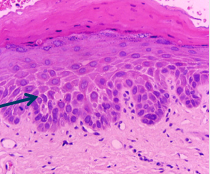

What does the arrow indicate on this slide, and what implication do these cells have with regards to diagnosis?

Cell atypia - changes within the cell.

They can be found in both cancerous and non-cancerous cells, so not necessarily and indication of cancer.